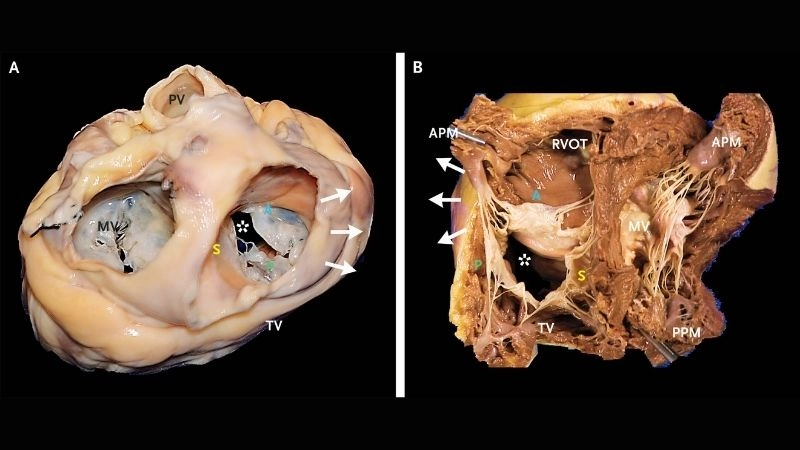

Images visual examples of Tricuspid Regurgitation (Insufficiency)

Visual examples often show an enlarged right atrium and ventricle, with abnormal blood flow patterns detected through echocardiography. These images help illustrate the mechanical dysfunction that contributes to the disease.

Tricuspid Valve Regurgitation affects blood flow in the right heart

Severe Tricuspid Regurgitation can lead to right heart failure